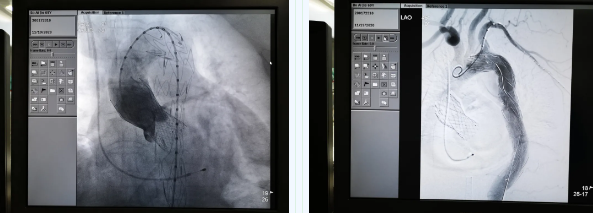

11月19日,西安國(guó)際醫(yī)學(xué)中心醫(yī)院心臟外科TAVR團(tuán)隊(duì)在心臟病醫(yī)院張金洲副院長(zhǎng)主持下,順利完成一例罕見“經(jīng)股經(jīng)導(dǎo)管主動(dòng)脈瓣置換術(shù) 經(jīng)導(dǎo)管主動(dòng)脈腔內(nèi)隔絕術(shù)”。經(jīng)查閱文獻(xiàn)證實(shí),此一站式復(fù)合手術(shù)國(guó)內(nèi)尚未見報(bào)道。由此,西安國(guó)際醫(yī)學(xué)中心醫(yī)院心外團(tuán)隊(duì)在心臟微創(chuàng)治療領(lǐng)域又向前邁進(jìn)了一大步。

張金洲副院長(zhǎng)關(guān)注著手術(shù)的每一個(gè)細(xì)節(jié),從建立軌道、跨瓣、釋放瓣膜、支架定位、造影和食道超聲確認(rèn),每一步都緊張而有序地進(jìn)行著。為了最大程度保障病人安全,心臟外科程亮副主任也帶隊(duì)建立動(dòng)靜脈入路,以備緊急體外循環(huán)。經(jīng)過(guò)團(tuán)隊(duì)每一位成員的密切配合,在近四小時(shí)的緊張奮戰(zhàn)之后,“TAVR TEVAR”復(fù)合手術(shù)順利完成;經(jīng)過(guò)造影和食道超聲證實(shí):人工主動(dòng)脈瓣無(wú)返流無(wú)瓣周漏、冠脈顯影良好,主動(dòng)脈覆膜支架無(wú)內(nèi)漏無(wú)移位。